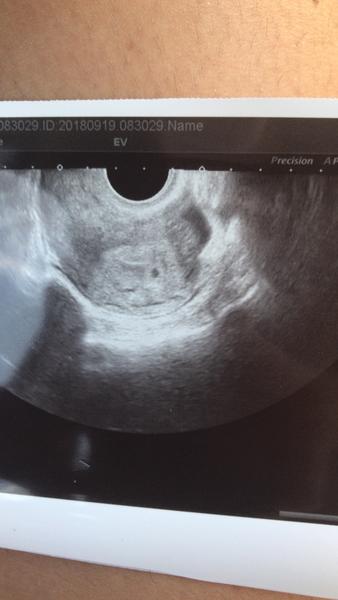

@felis první je v den očekávané MS a druhý 14dpo což bylo asi 4+1

@felis tenhle je 4+2